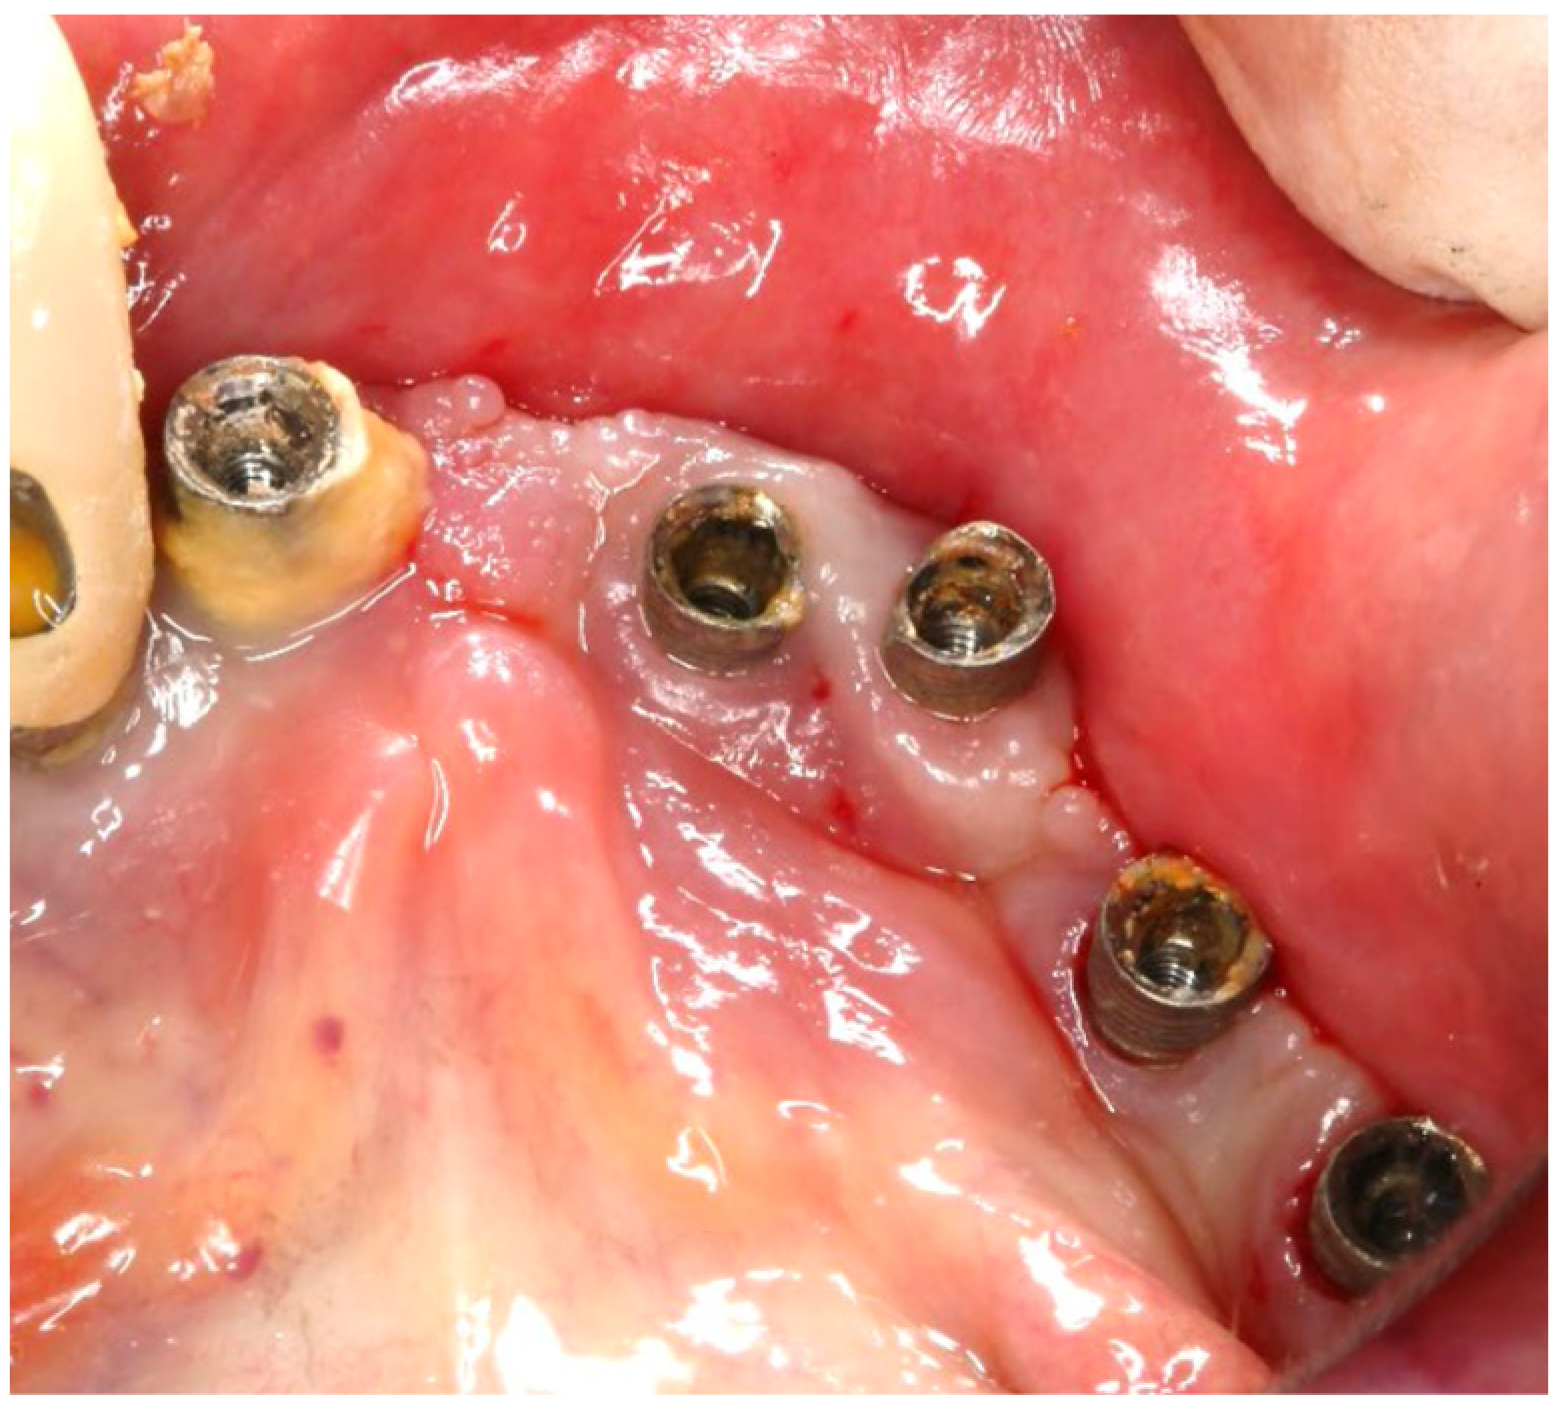

In this case, after achieving the renewed implant surface (machined), the regenerative procedure involving bone grafting and collagen membrane was not performed. The flaps were repositioned and secured with tension-free primary closure. The postoperative instructions included chlorhexidine 0.12% (Taro Pharmaceuticals, Haifa Bay, Israel) rinses and systemic antibiotic coverage for 5 days. Regular clinical and radiographic evaluations were conducted at 1 month, 3 months, 6 months, and 12 months, postoperatively. At the six-month follow-up, the clinical examination revealed significant improvements, with resolution of inflammation and no BoP; the patient reported a complete resolution of the initial chief complaints. Radiographs demonstrated stabilization and initial signs of bone regeneration around treated implants. At the 12-month follow-up, the bone level and PDs were stabilized (Figure 23), and the implant surface adequately accommodated the gingival tissue (Figure 24).

Figure 23. Radiographic bone level and probing depth comparing the baseline and 12-month results.

Figure 24. (a) Clinical follow-up after 12 months; (b) Radiographic outcome after 12 months.